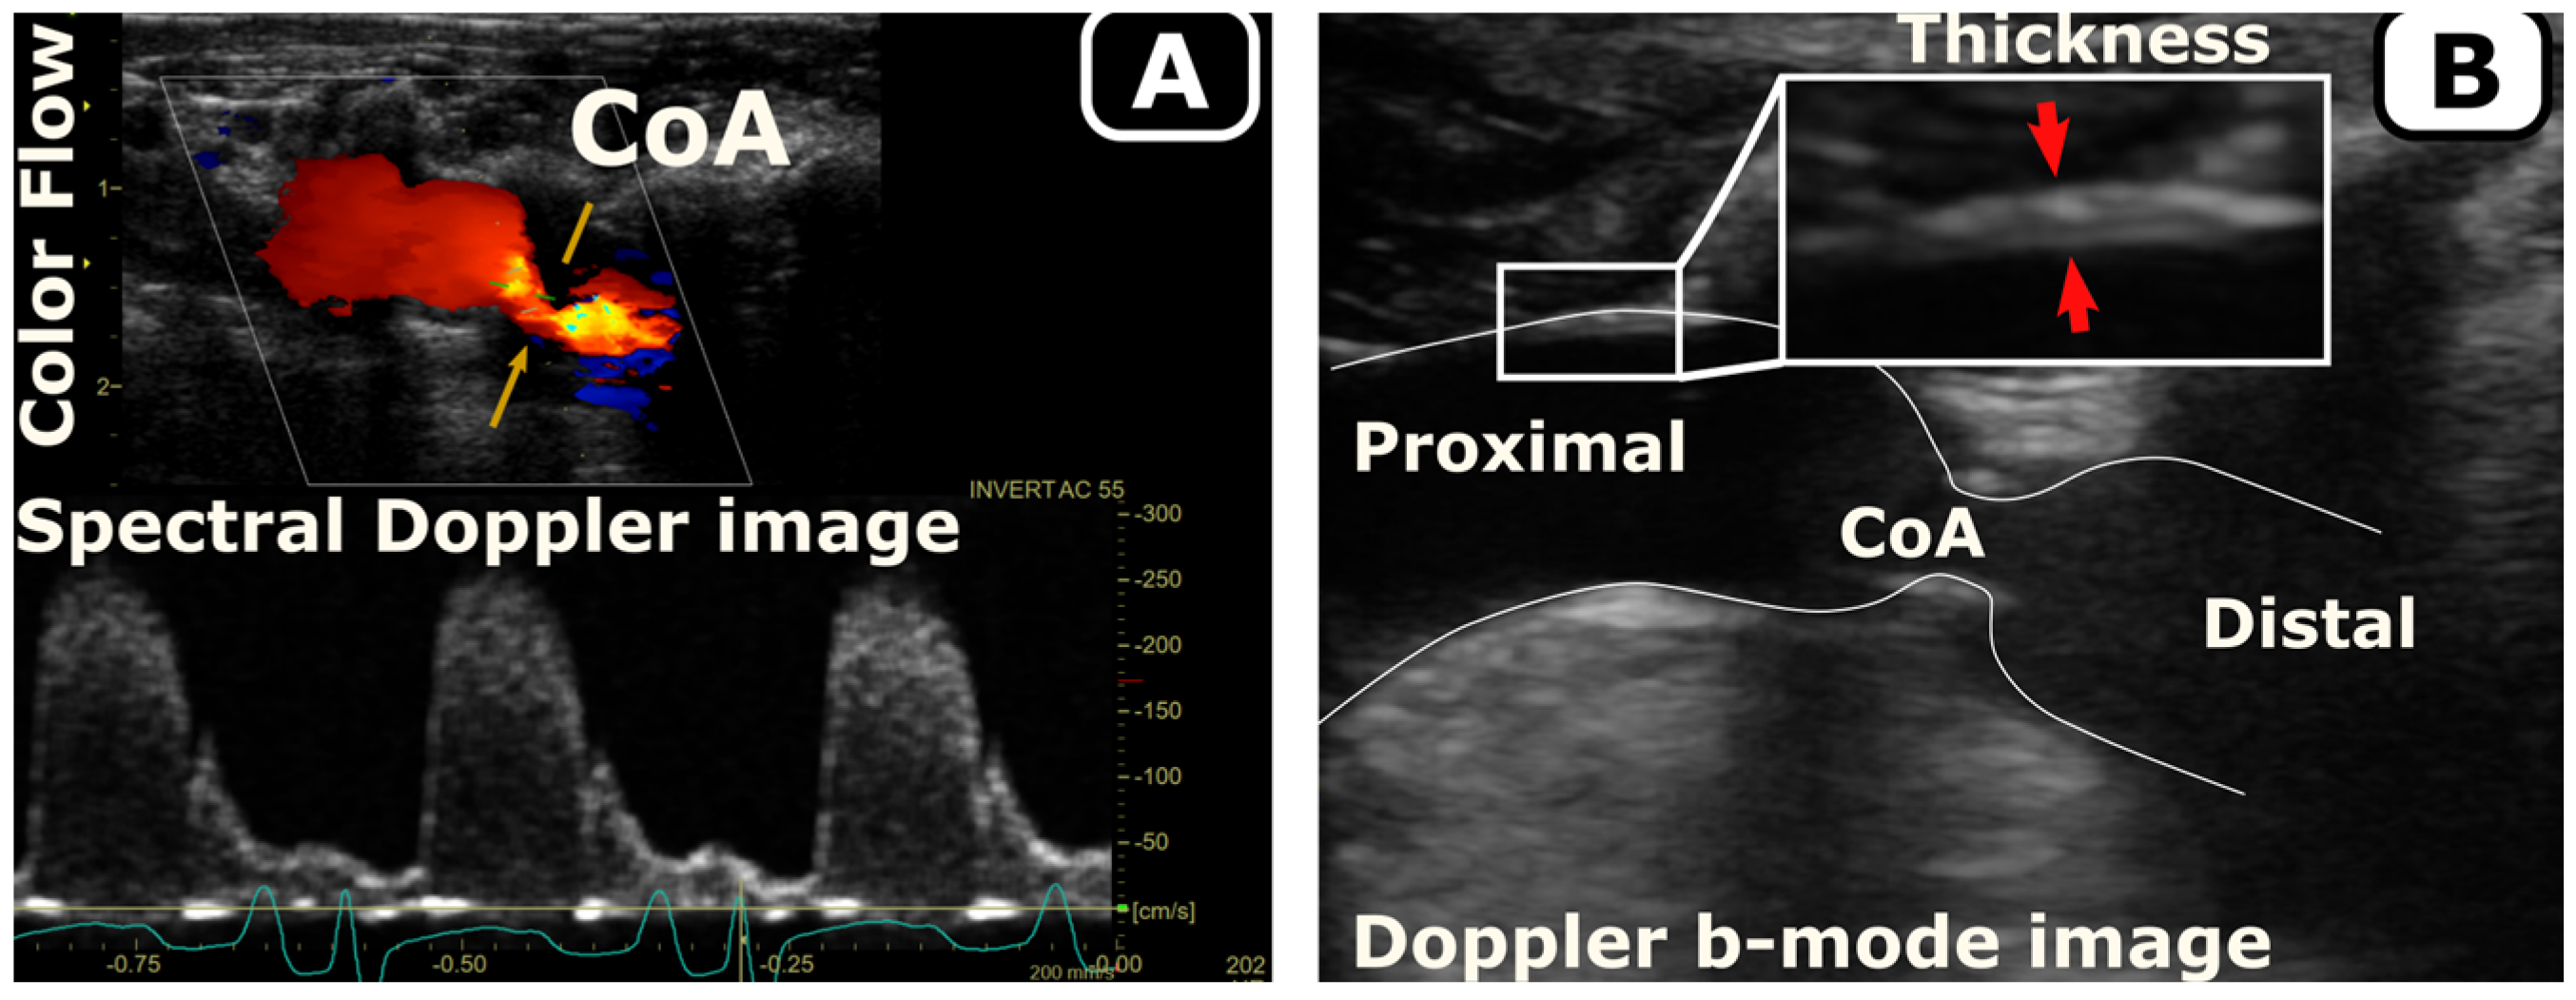

2.5.2. Temporal Monitoring of Morphology and Hemodynamics

2.5.3. Vascular Stiffening

2.5.6. WSS and IWS Evolution